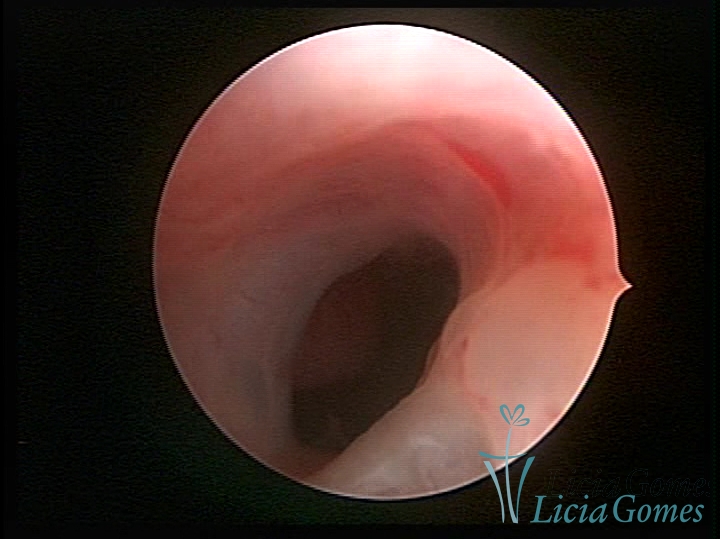

Sinéquia TIPO FIBROSA

As Sinéquia uterinas são cicatrizes (aderências) entre as superfícies das paredes uterinas, que podem ocorrer após manipulação cirúrgica, ou curetagem uterina, ou após um processo inflamatório na cavidade uterina (endometrite), podendo levar a alterações menstruais, infertilidade, e complicações obstétricas, como abortamento, parto prematuro.